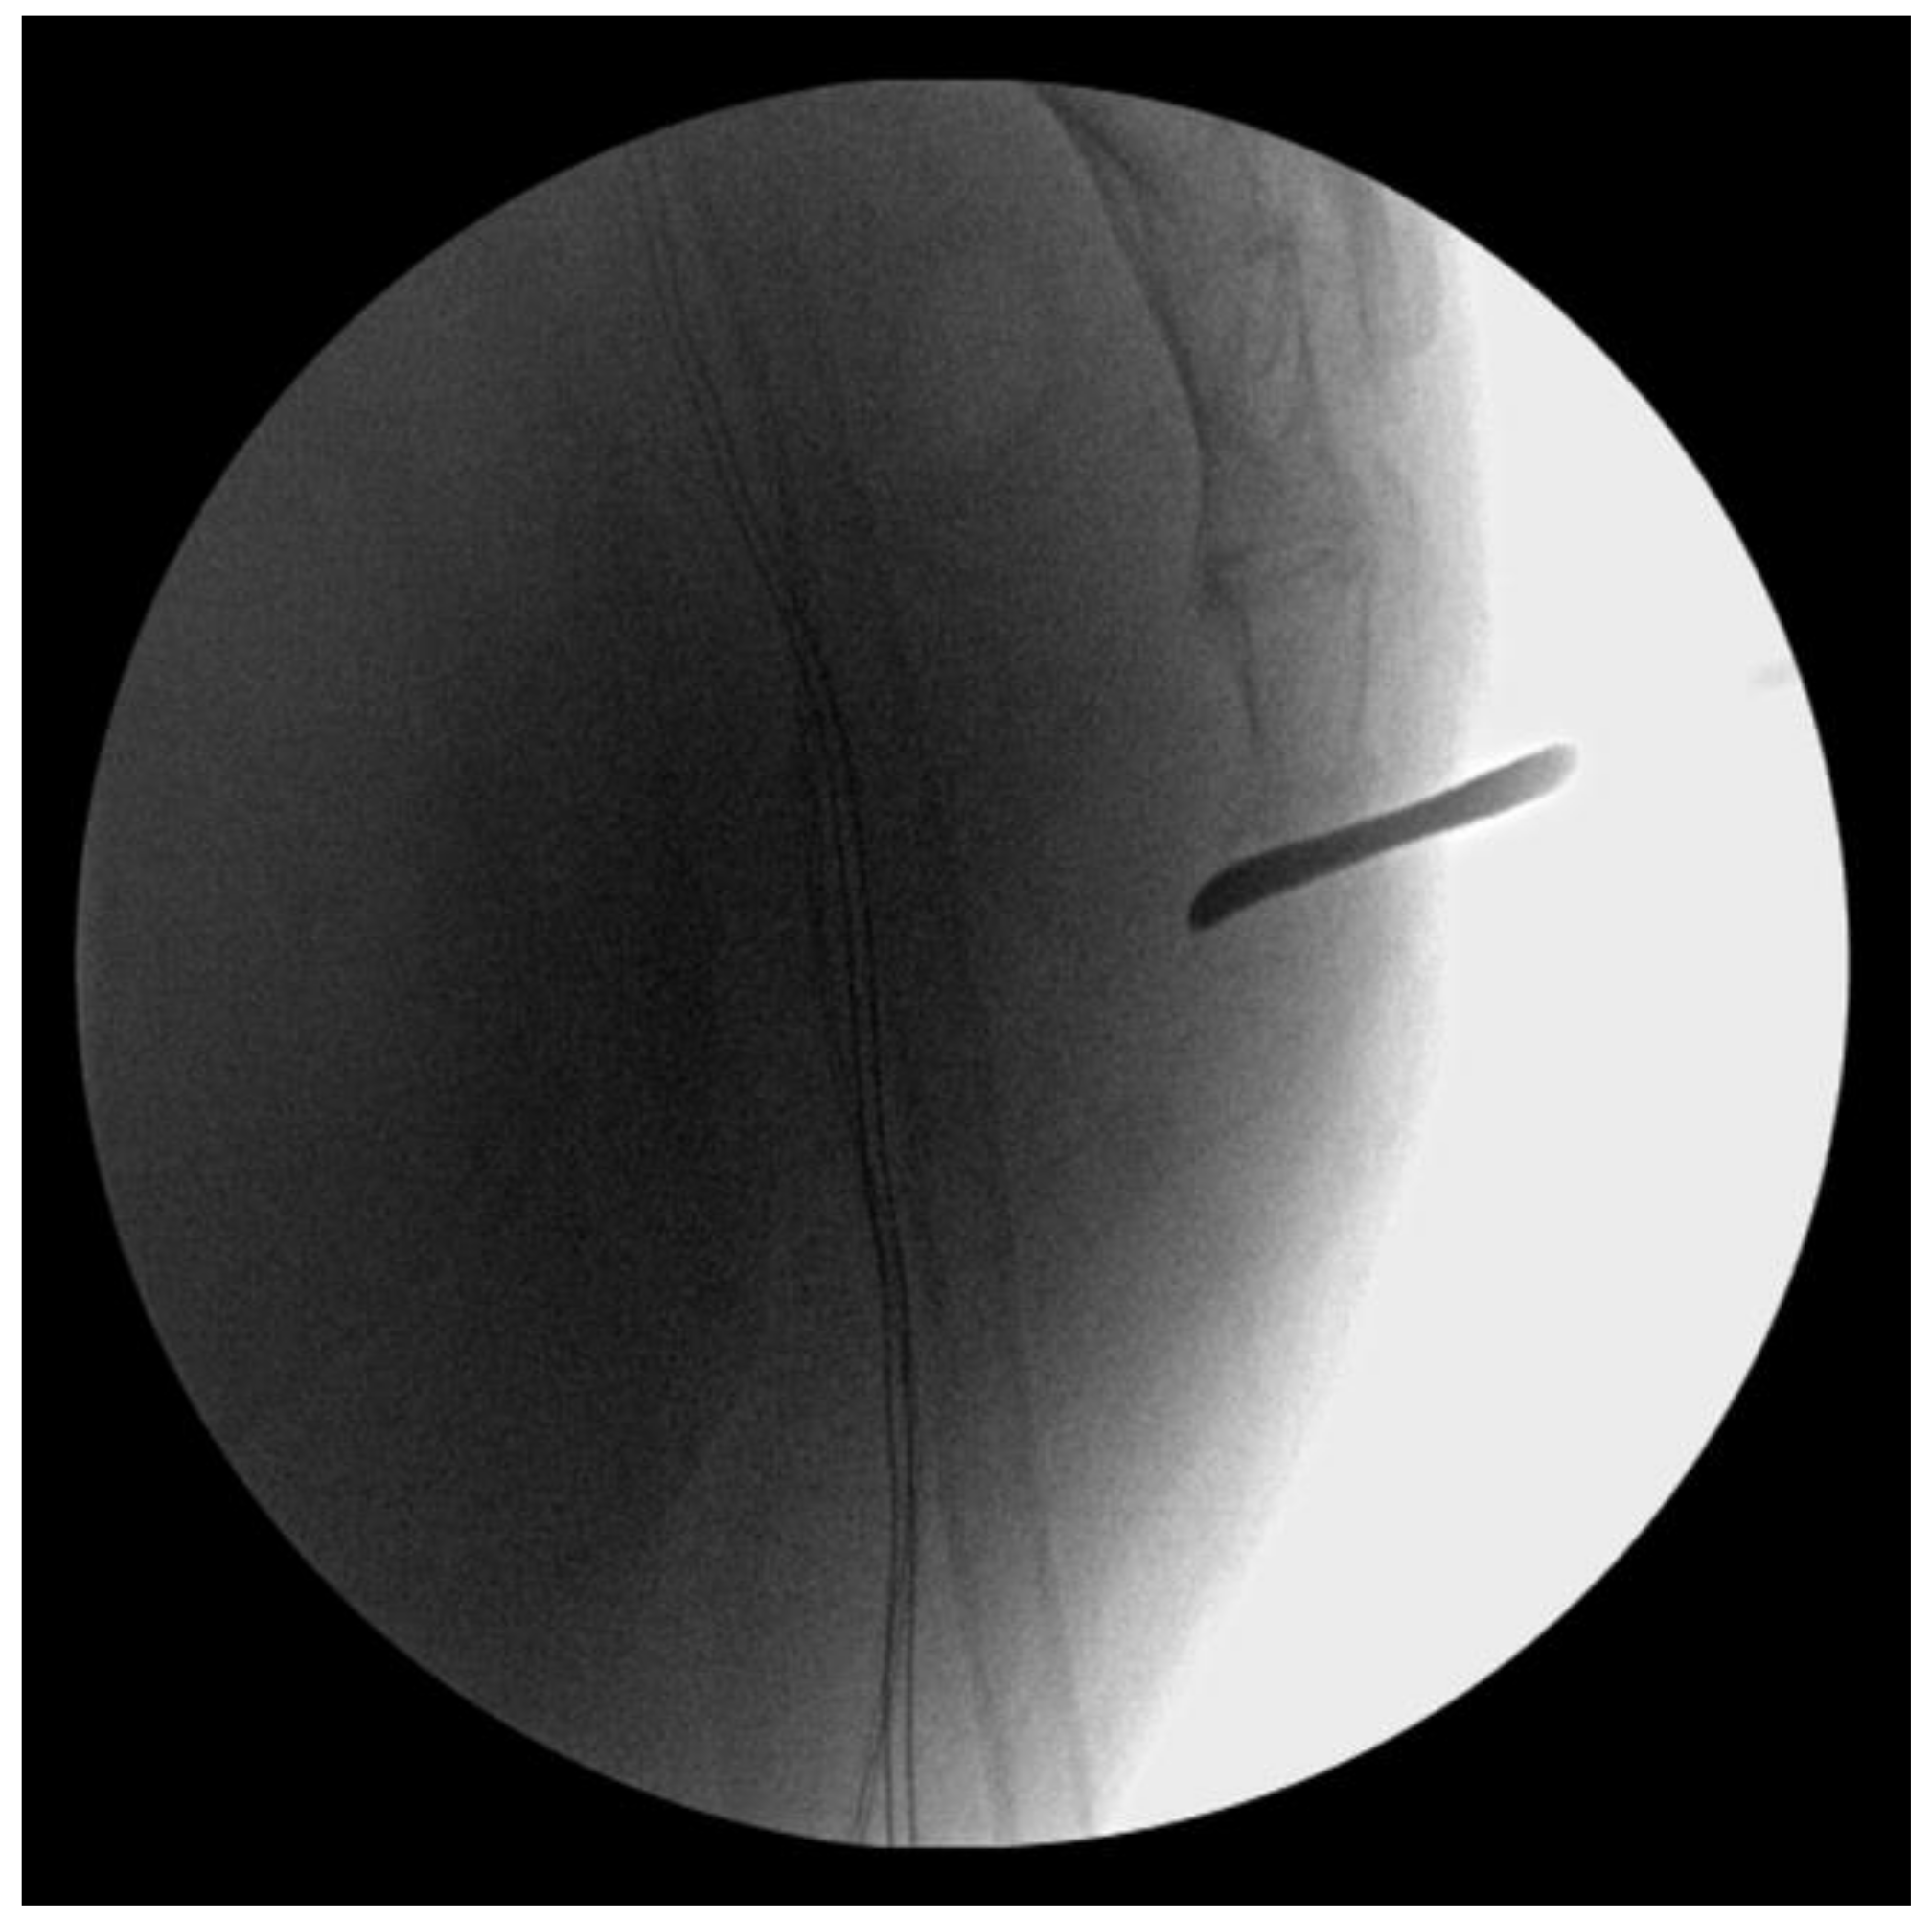

The patient underwent surgery under general anesthesia in a prone position. Before making an incision, manual reduction was attempted via the rectum under intraoperative fluoroscopy, but it failed (Figure 2).

Figure 2. Intrarectal manipulation was attempted before open reduction, but the dislocated coccyx was not reduced.